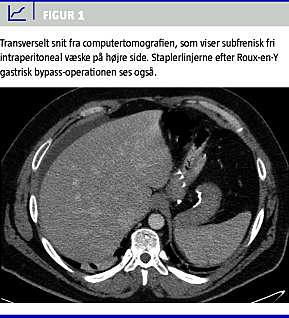

Siden operationen havde han haft et vægttab på 15 kg, og der havde ikke været postoperative komplikationer. På indlæggelsesdagen fik han pludseligt indsættende øvre abdominalsmerter. Han var direkte palpationsøm i epigastriet og under højre kurvatur. Resultaterne af standardblodprøver viste normale forhold. Efter indgift af intravenøs og peroral kontrastvæske blev der foretaget en akut abdominal CT med rekonstruerede billeder i tre projektioner. CT'en viste ascites (Figur 1 ) samt strækning og rotation af mesentericakarrene som tegn på mulig begyndende intern herniering. Der var ikke umiddelbart tegn til fri intraperitoneal luft eller gastrisk blowout . På grund af fri væske og abdominale smerter blev det besluttet at foretage akut diagnostisk laparoskopi.

Ved første gennemgang af CT-billederne kunne radiologen ikke påvise fri intraperitoneal luft, men efter information om operationsfundet kunne man på et af transversalbillederne se en yderst diskret lille luftlomme umiddelbart uden for det aflukkede segment (Figur 2 ).